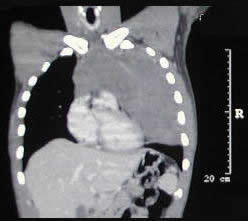

un paciente joven, con un gran tumor del mediastino anterosuperior de rápido

crecimiento, correlacionando su tamaño entre la radiografía

del tórax y los hallazgos tomográficos realizado 15 días

después, y las condiciones físicas al momento de su intervención,

con gran dificultad respiratoria.